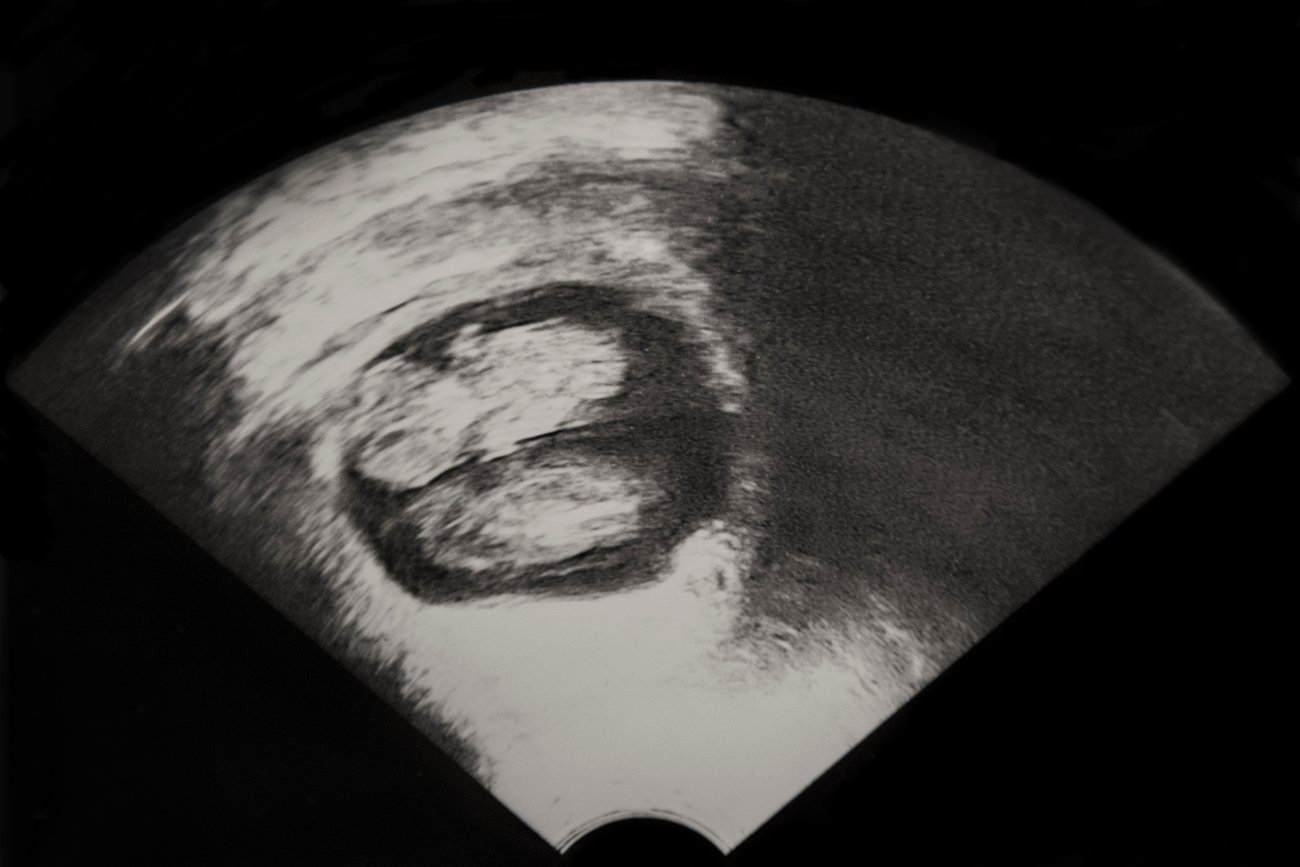

Zwillinge Ultraschall 7 Ssw. Wie entstehen Zwillinge? Alle Fakten zu ihrer Entwicklung Entwicklung, Symptome, Ultraschall und Tipps für eine gesunde Zwillingsschwangerschaft Bei eineiigen Zwillingen ist im Ultraschall deutlich zu sehen, dass sie sich eine Embryonalhülle teilen

SSW 7: Das Babys misst etwa 6mm Alles über den Mutterpass Papa und die Schwangerschaftshormone SSW: Zweieiige Zwillinge: Zwei getrennte Plazenten: 7 Ob die Zwillinge eineiig oder zweieiig sind, ist im Ultraschall am besten zwischen der achten und der zwölften Schwangerschaftswoche zu erkennen

7. SSW Die 7. Schwangerschaftswoche auf einen Blick NetMoms.de. Er schlägt mit erstaunlichen 100 bis 140 Schlägen pro Minute SSW 7: Das Babys misst etwa 6mm Alles über den Mutterpass Papa und die Schwangerschaftshormone

7. Schwangerschaftswoche Ultraschall Pregnant Health Tips. SSW sogar der Herzschlag des Babys wahrgenommen werden Entwicklung, Symptome, Ultraschall und Tipps für eine gesunde Zwillingsschwangerschaft